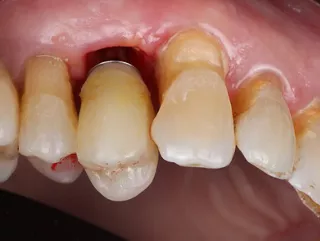

Dr. Fabian Hirsch, Germany In this case the treatment plan required extraction and involved a combination of Axiom X3® TL and Axiom X3® BL implants. Read more